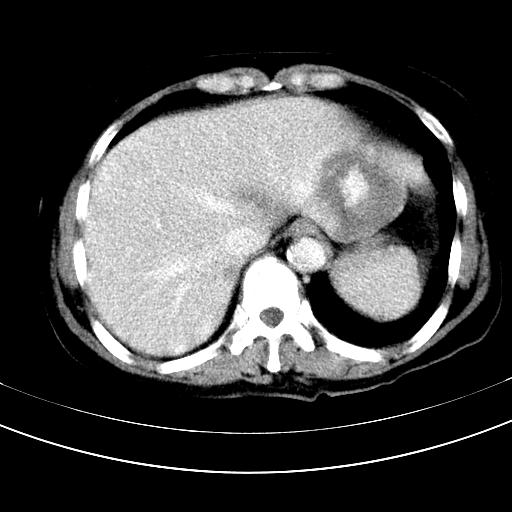

补充强化片

胃内见充盈缺损,建议行胃镜病理检查,如果胃内无占位,则肝内考虑左叶、尾叶为包膜型肝癌,如有则考虑为转移瘤,左侧肾上腺 明显增大,成结节改变,本人考虑转移瘤可能性大。

肾脏前方的是什么,肾上腺吗,

考虑:胃体小弯侧胃癌(或平滑肌瘤恶化或平滑肌肉瘤)伴肝转移,左侧肾上腺转移不除外.

胃癌肝内转移及肾上腺转移。

胃窦部占位伴肝及左肾上腺转移可能大,建议增强扫描。

谢谢楼主的增强片子,平扫没发现左侧肾上腺的问题很不好意思,可惜片子只有门脉期,所以还只有猜,肝脏的病灶在门脉期部分强化,首先考虑为血管瘤(其他的用一种病不好解释)胃要喝水就好了现在不好说是否有问题,左肾上腺的问题考虑是肿瘤。